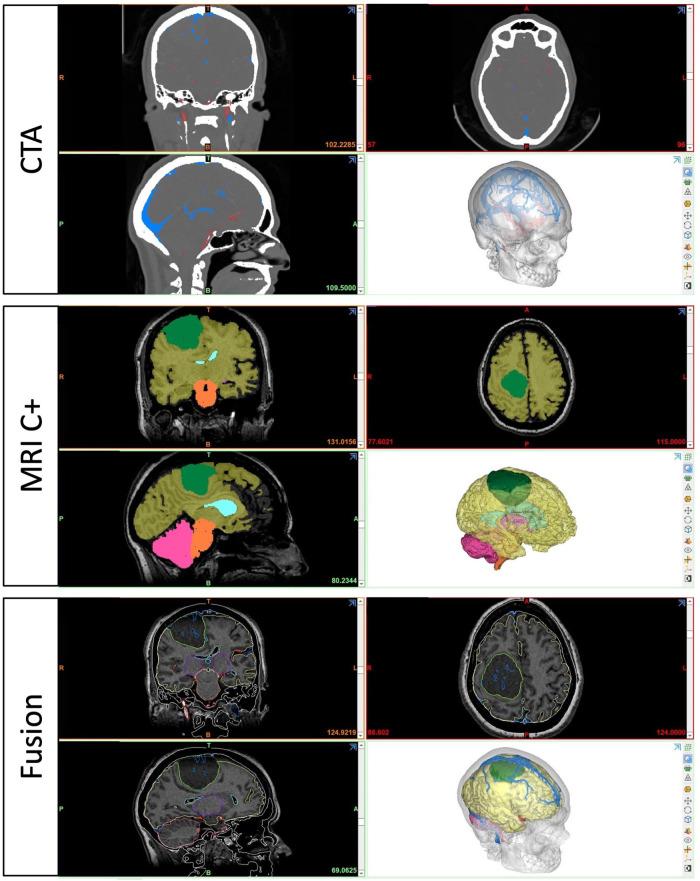

A patient-specific 3D digital model of parasagittal meningioma case was constructed. Participants were invited to plan the incision and craniotomy first after the conventional planning session with MRI, and then with 3D model. A feedback survey was performed at the end of the session. Quantitative metrics were used to assess the performance of the participants in a double-blind fashion.

方法